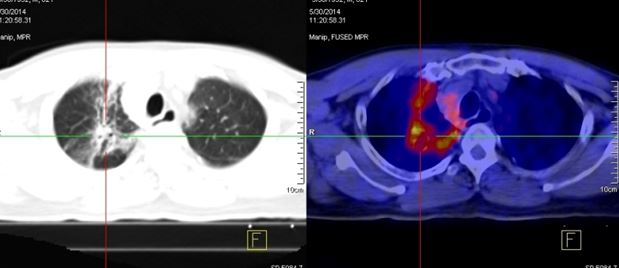

Hình ảnh PET/CT sau khi kết thúc liệu trình điều trị 1 tháng:

Kết quả PET/CT tháng 05/2014: tổn thương thùy trên phổi phải tăng hấp thu FDG nhẹ, theo dõi viêm sau xạ trị.